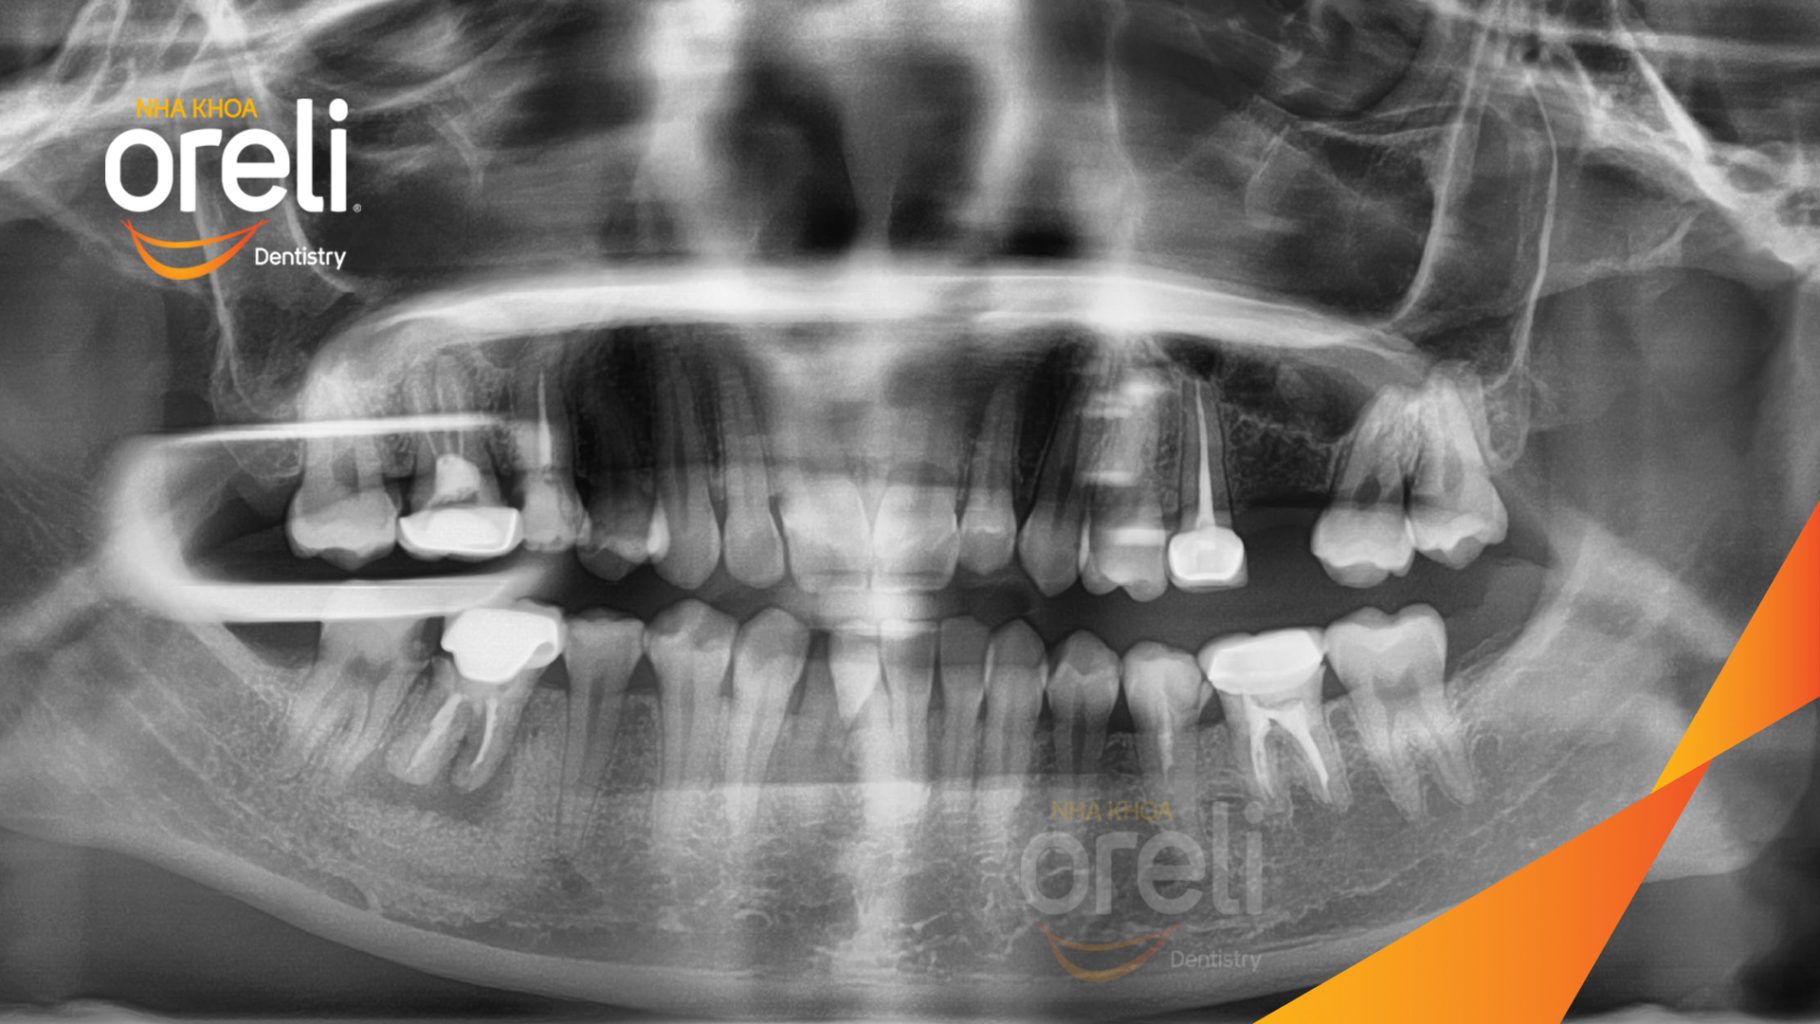

Ca niềng hạng 3 móm di gần răng 78 cho nụ cười đẹp ở Oreli

Ca niềng răng di gần răng 7 8 phục hồi ăn nhai và thẩm mỹ nụ cười. Kết quả thực tế trước và sau điều trị tại Nha khoa Oreli.